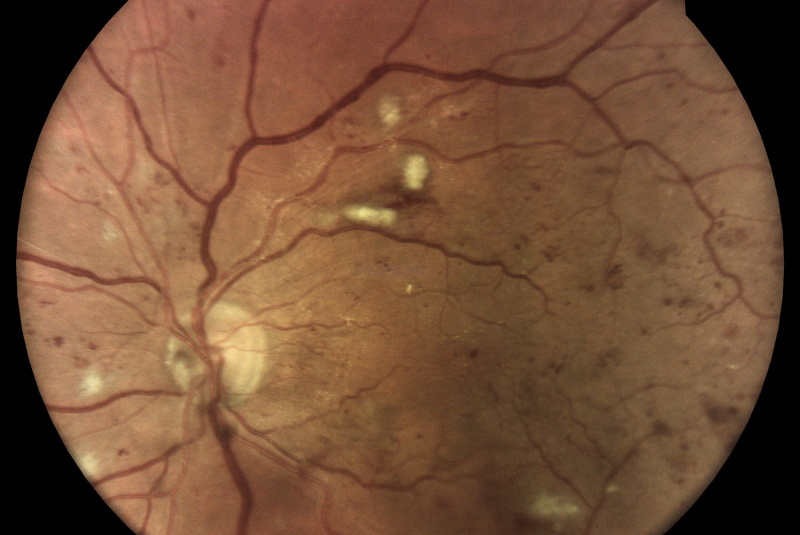

AI (umělá inteligence) okamžitě rozpozná práznaky diabetické retinopatie a klasifikuje výsledky podle závažnosti na základě mezinárodních klasifikací. Získáte přehled s hodnocením závažnosti záchytu, kde po analýze snímků zachycených kamerou iCare DRS Plus je automaticky generován report o pacientovi se stupnicí závažnosti pro diabetickou retinopatii na základě mezinárodních standardů (ICDR, AREDS).

Fundus kamera iCare DRSplus pořídí celkem 4 vysoce kvalitní True Color snímky (dva z pravého a dva z levého oka), které se automaticky ukládají na cloud a posílají se na zpracování AI - umělé inteligenci. Report je dostupný ihned a ten je možno konzultovat s pacientem během téže návštěvy u lékaře.